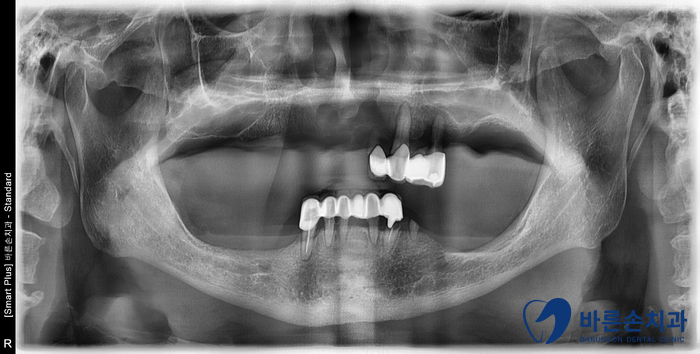

정확한 진단을 위해 파노라마 엑스레이를 촬영했습니다.

남아있는 치아도 치조골이 흡수되어 좋지 않고,

크라운 아래로 충치가 많이 진행되어 있습니다.

남아있는 치아 모두 발치 후

위에 4개, 아래 4개 총 8개의 임플란트를 심어 앞니를 브릿지로 만들고,

상, 하악 부분틀니가 필요하다는 진단이 나왔습니다.